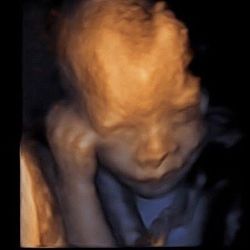

Chinchwadkar Sonography : I have been to many radiologist but dr.